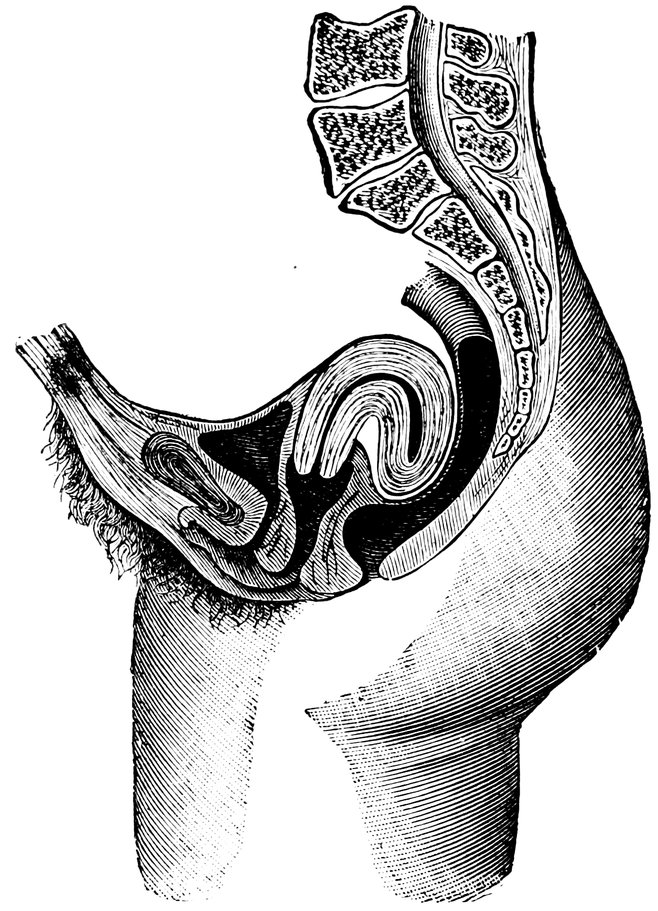

| 2. | Portion of the pelvic viscera in the female, etc. | 9 |

| 14. | Sagittal section of the female pelvis | 56 |

| 81. | Retroflexio Uteri (after A. Martin) | 520 |

Fig. 2.—Portion of the pelvic viscera in the female, and their relation to the muscles of the pelvic outlet (or perineal muscles), shown in the left half of the pelvis, seen from the right side.—The parametrium. (From Toldt: Atlas of Human Anatomy.—Rebman Company, New York.)